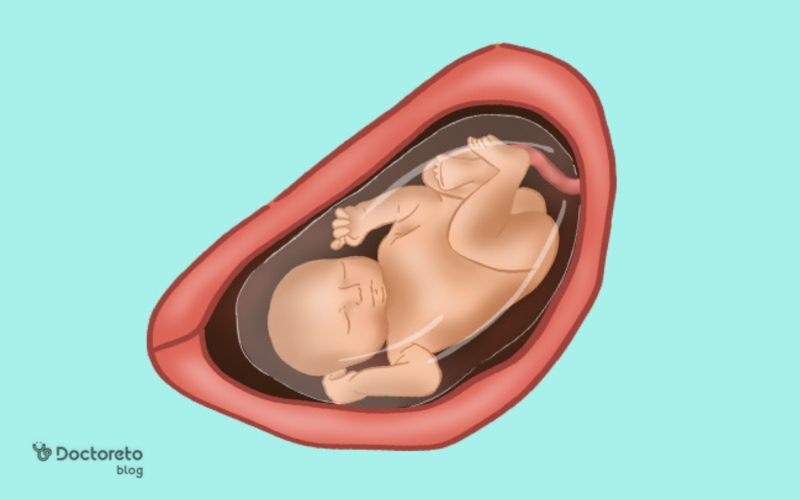

عکس جنین در هفته 32 بارداری

عکس جنین در هفته 32 بارداری جنین را در حالت خمیده نشان میدهد، با سر به سمت پایین و دست و پا نزدیک بدن. در این حالت، شکل کلی بدن، سر، دستها و پاها واضح و قابل تشخیص است و حرکات کششی و لگدهای او بهصورت سادهسازیشده دیده میشود. همچنین، جنین سی و دو هفته در این تصاویر تقریباً اندازه نهایی خود را یافته و حالت جمعشده داخل رحم را نشان میدهد.